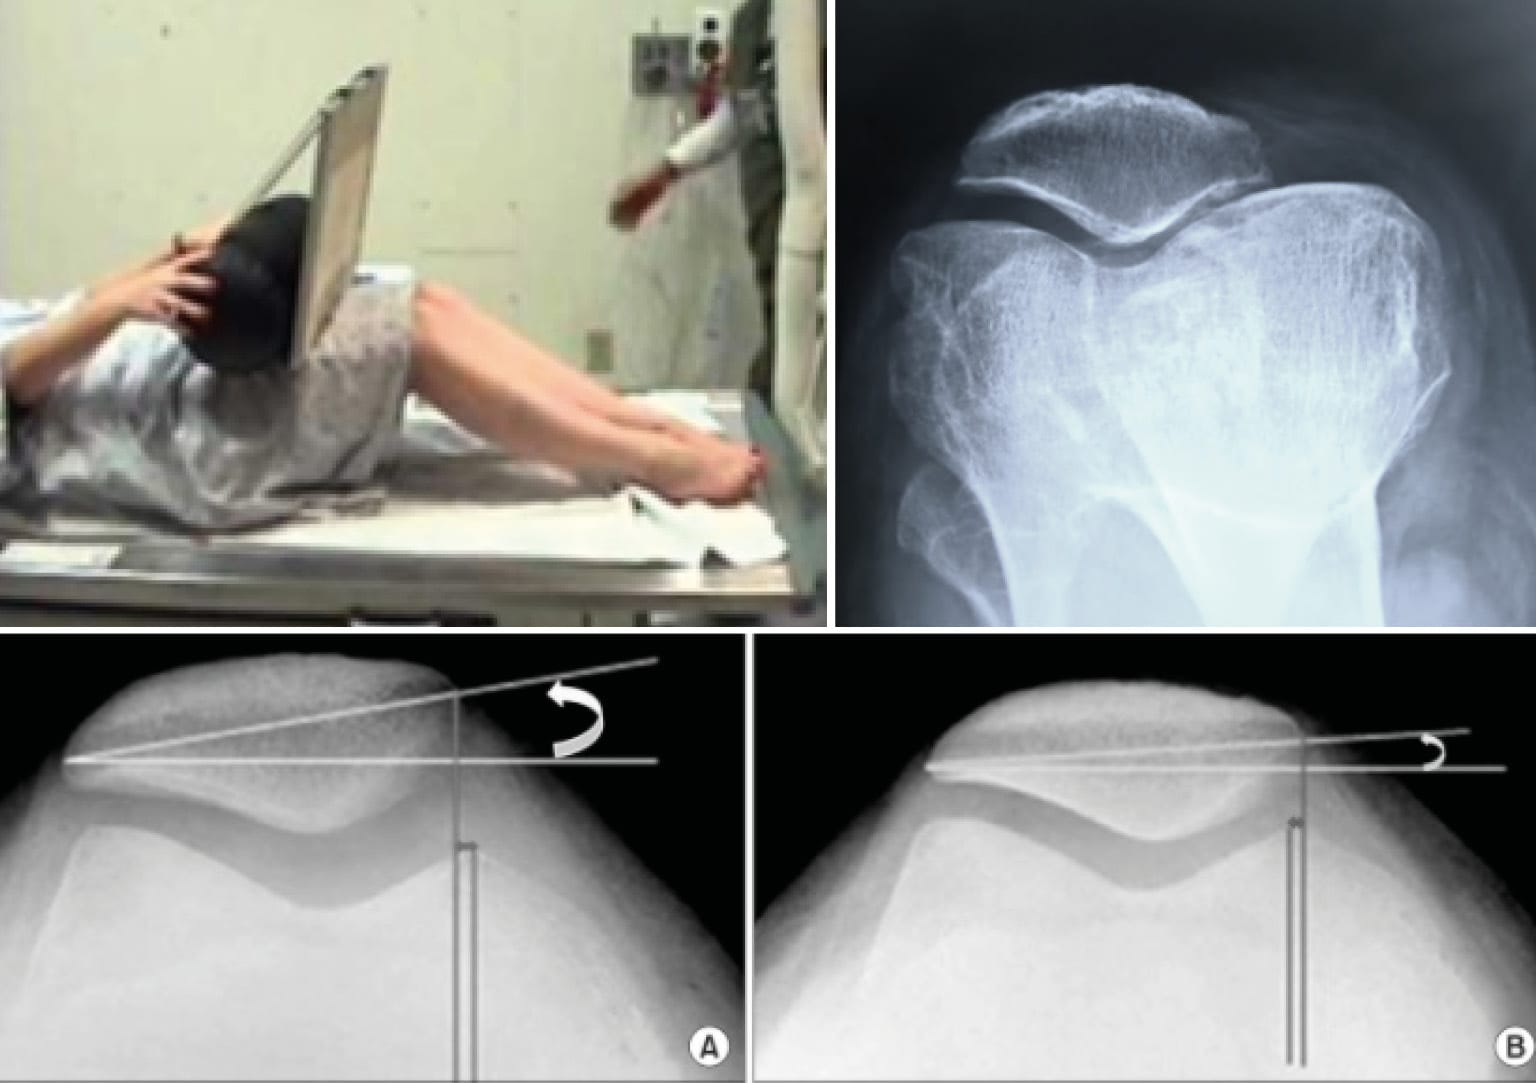

A good lateral X-ray of the knee meets specific criteria (Figure 14). It is performed at 30° of flexion with the two posterior condyles superimposed. To optimise this superimposition, a brief fluoroscopy may be performed. The patient can be lying on the X-ray table or in single-leg stance.

The axial view of both patellae must be performed with both knees flexed at 30° and no more, as is too often the case. Both knees are on the same cassette. We no longer request a series of views with the knee flexed at 60° and 90° or in external rotation.

The axial view (Figure 16) is conventionally performed at 30° of flexion. It does not account for the proximal part of the trochlea. The lateral X-ray allows for the analysis of the trochlea from its most proximal part down to the notch.